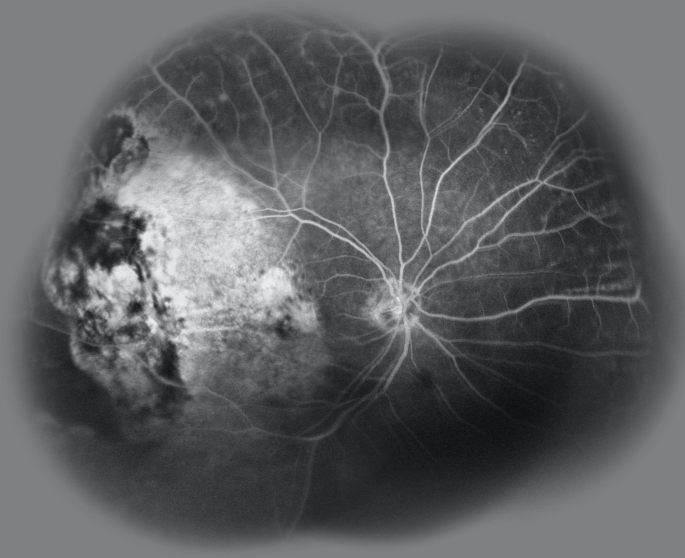

Multiple microaneurysms, edema and capillary damage in a non diabetic.

77 you WM with a chronic Hx of multiple microaneurysms, advanced edema and capillary damage in one eye and the other is normal. No diabetes, mild HTN. Treated with anti VEGF and focal laser over the years sucessfully but keeps returning with new areas of leakage and new MA’s. Diagnosis and treatment options?